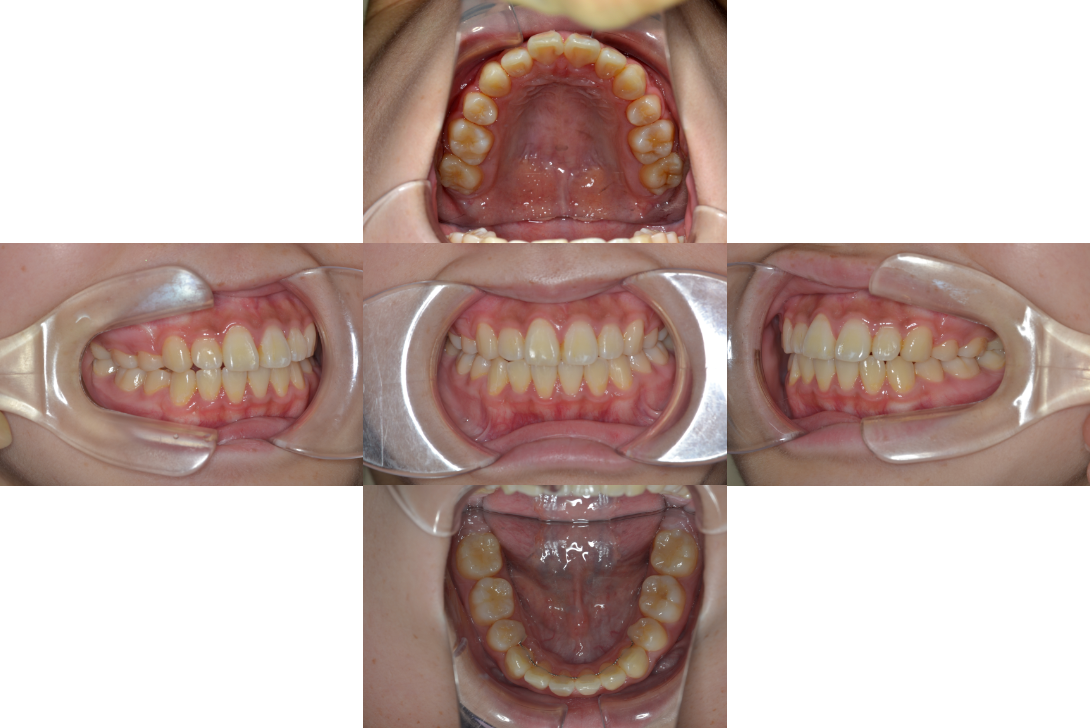

叢生を抜歯とDBSで改善した症例

※DBSとはダイレクトボンディングシステムと呼ばれており、ブラケットにワイヤーを通して歯を動かしていく矯正治療です。

患者情報

17歳女性

主訴

歯並びがガタガタ

行った治療内容

上下顎両側4番抜歯、DBS

治療のリスク

歯肉退縮、歯根吸収

治療期間

動的治療期間3年6か月

※ クリックして拡大することができます。